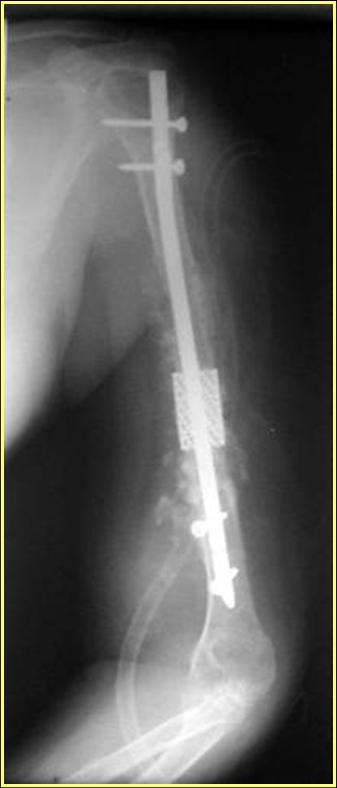

Типичная положительная ситуация для интрамедуллярного остеосинтеза с

использованием опорного металлокаркаса для компенсации дефекта.

Рентгеновская версия реконструкции. хронология:

после операции, 2 мес. после операции, через 1 год

Движения в полном объеме восстановлены к 2 мес. после операции. Если надо могу показать мультик. Сейчас уже прошло более 3 лет, больная не

показывается. Успехов ЛАФ.